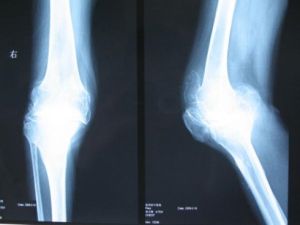

檢查

診斷骨刺可以利用放射線學檢查,及電性診斷。下面我們進行一下詳細的介紹:

1.X光檢查

包括正面、側面、斜面、前屈、後仰,以了解脊椎情形。